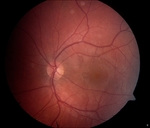

Best-corrected visual acuity was 20/25 in both eyes. Intraocular pressure, pupil response, and anterior segment examination was normal in both eyes. Posterior segment examination of the left eye was normal. Within the macula of the right eye, there was a circular, well-circumscribed, yellow-orange subretinal lesion centered at the fovea. There was no vitreous cell or haze and the optic nerve and the remainder of the peripheral retina appeared normal.

| Lead Image: Color fundus photograph of the right eye showed a well-circumscribed, hypopigmented, macular lesion with foveal pigmentary changes. |